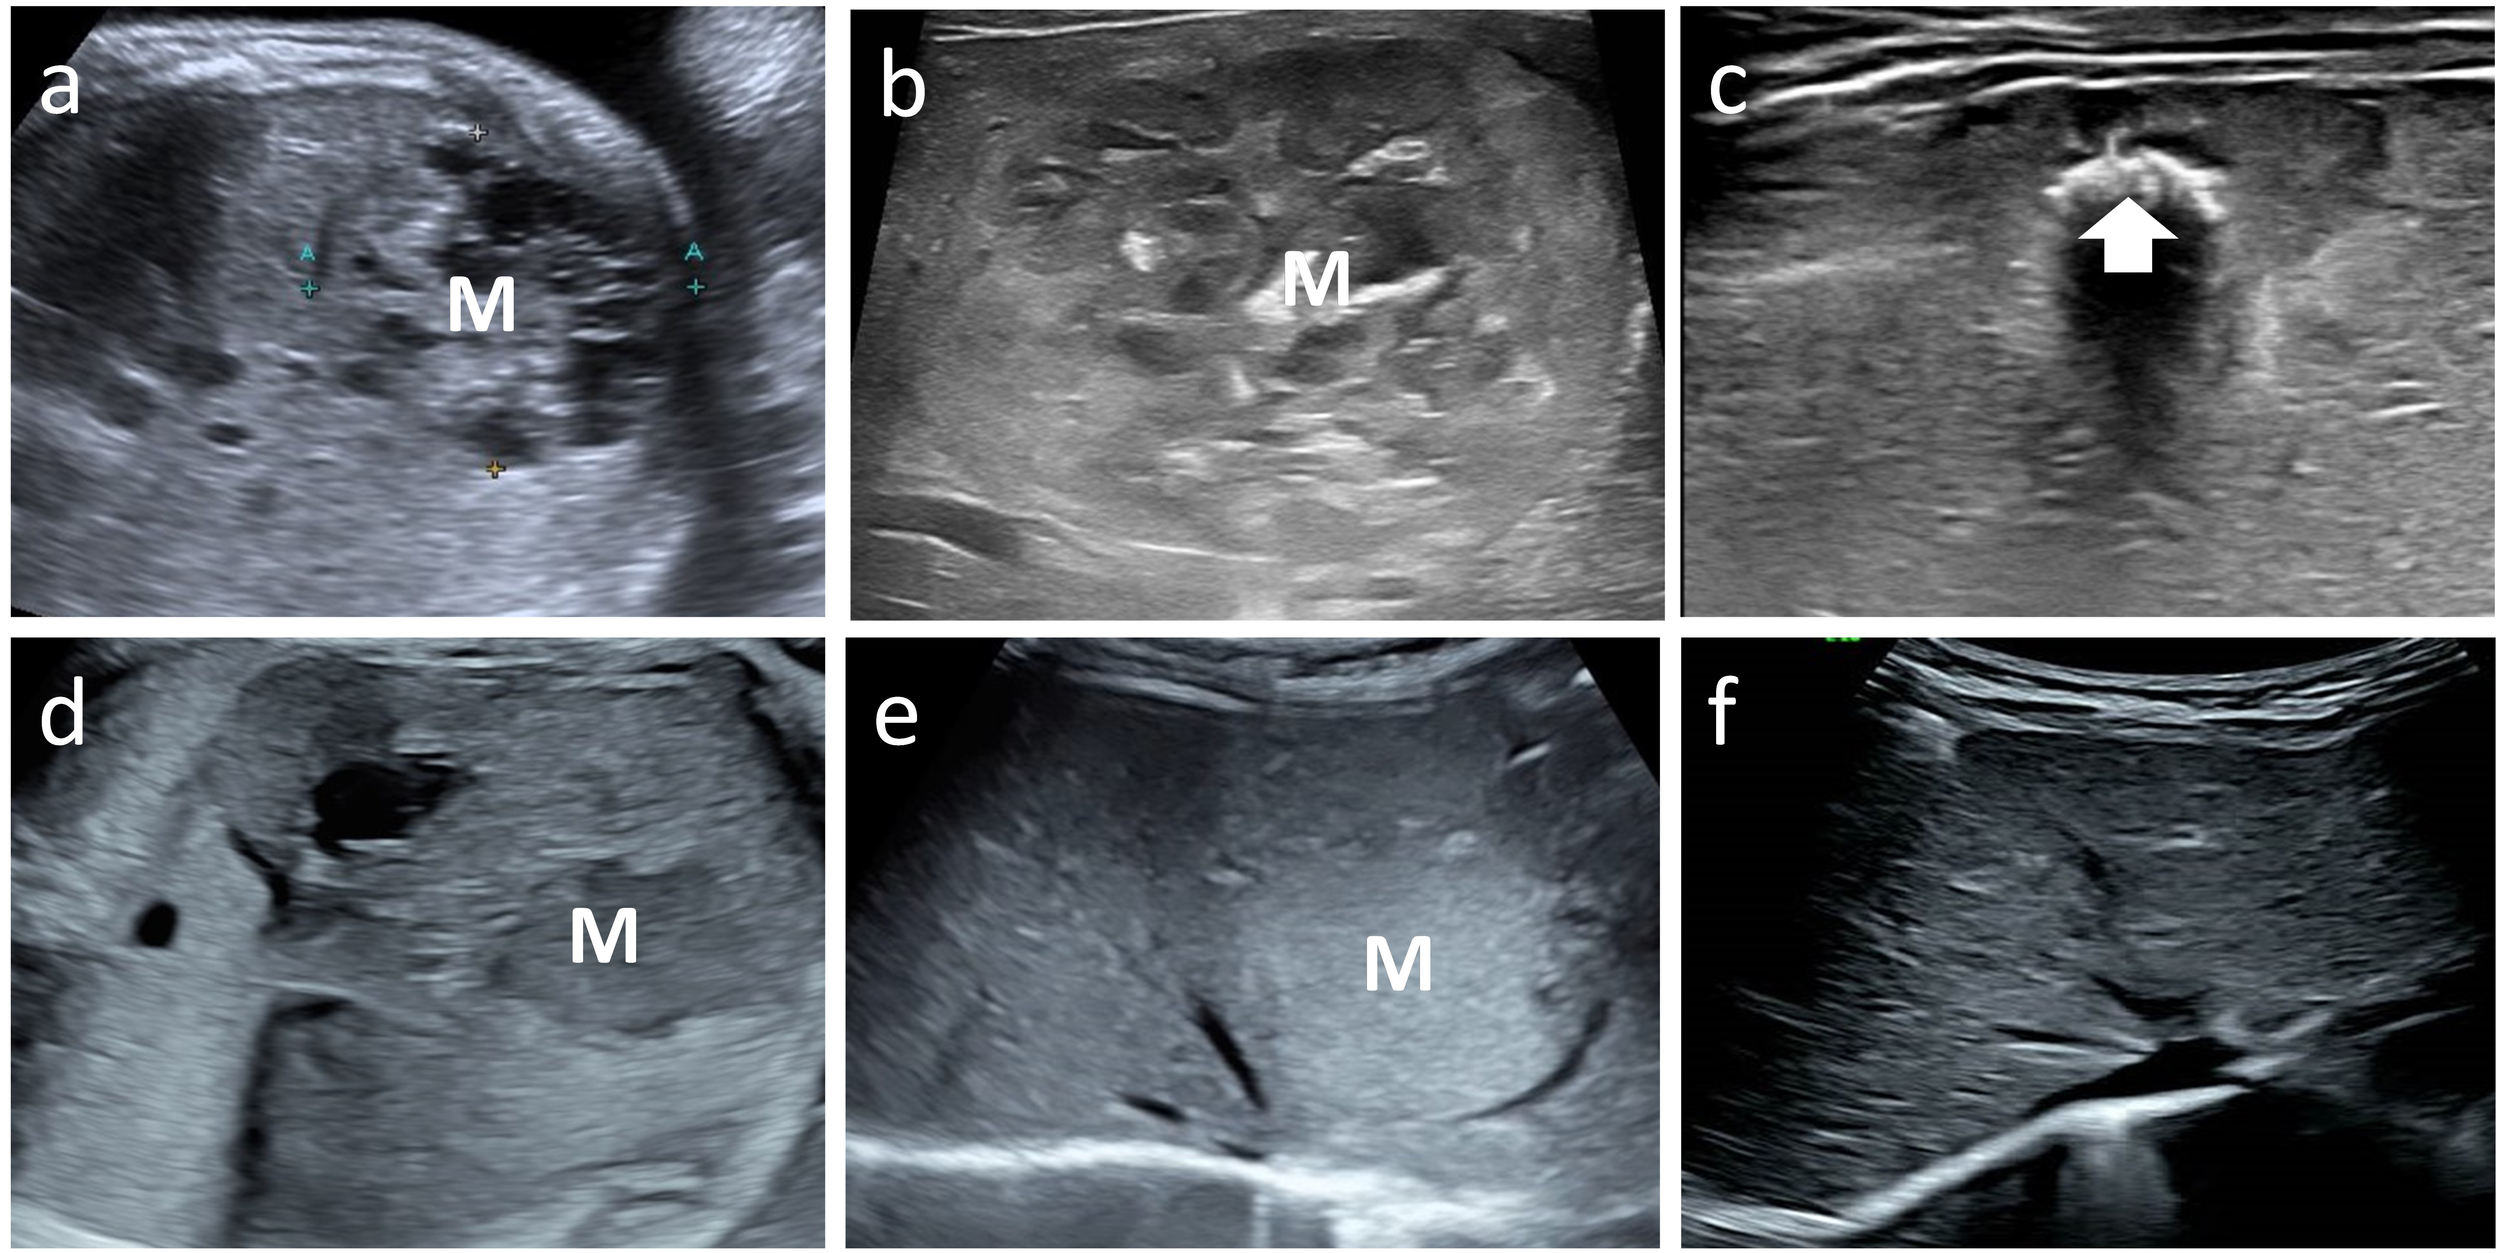

Figure 4

Ultrasound images labeled a to f. Panels a, b, d, and e show cross-sections with a marked “M”, likely indicating an area of interest. Panel c displays an area with a highlighted section marked by an arrow. Panel f has a different orientation or view, depicting varied tissue structure.

Figure 4. Case 6 and 8 with mass (M) on fetal ultrasound, postnatal ultrasound with maximum volume and follow up image showing regression. Case 6 fetal and postnatal images (a, b) show internal heterogeneous, honeycomb hypoechogenicity. The tumor volume peaked at 112 ml. The final regression image (c) shows patches of echogenic calcification (arrow). Case 8 fetal and postnatal images (d, e) show a homogeneous mass, hypoechoic on prenatal ultrasound and hyperechoic on postnatal ultrasound. The tumor volume peaked at 13 ml. The tumor eventually regressed completely (f).